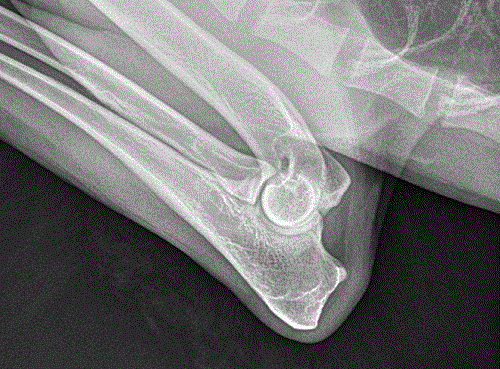

Elbows: OFA Normal